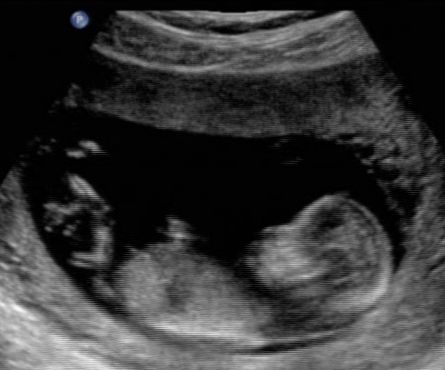

The SECOND thing that we're growing is our very own little embryo! That's right - we are expecting the tiniest Thurner on March 24, 2011 - making me 10 weeks impregnated (which sounds way more cool than "pregnant"). Warning: this is a long post! I've got a lot to tell you, dear blogging friends. Both for your random knowledge and my own memories.